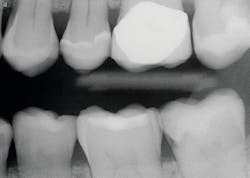

Luting characteristics on internal crown and external prep surfaces

The internal surfaces of current zirconia crowns are usually very smooth (figure 2). If the prep is adequate as described, this is usually not a problem. If there is any question about the potential zirconia crown retention, roughen the internal surfaces of the crown with a coarse diamond. If you do this, make sure you use a 3Y class 5 ceramic material. Many zirconia brands have modified material formulas that will not tolerate adjustment with a coarse diamond and will break. Similarly, roughen the external axial walls of the inadequate tooth preparation.

All brands of the most popular cement types are either resin or resin-modified glass ionomer. They are resilient! Lack of luting irregularities on the internal surfaces of the prep and the crown may allow the crowns to come off during service because the cement is resilient.